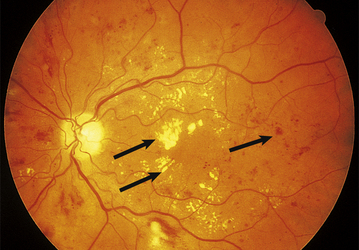

Vascular disease 794

Macular degeneration 796